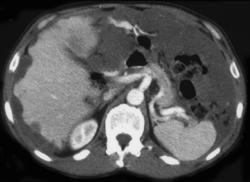

Recurrent Tumor at Gastrojejunostomy Site